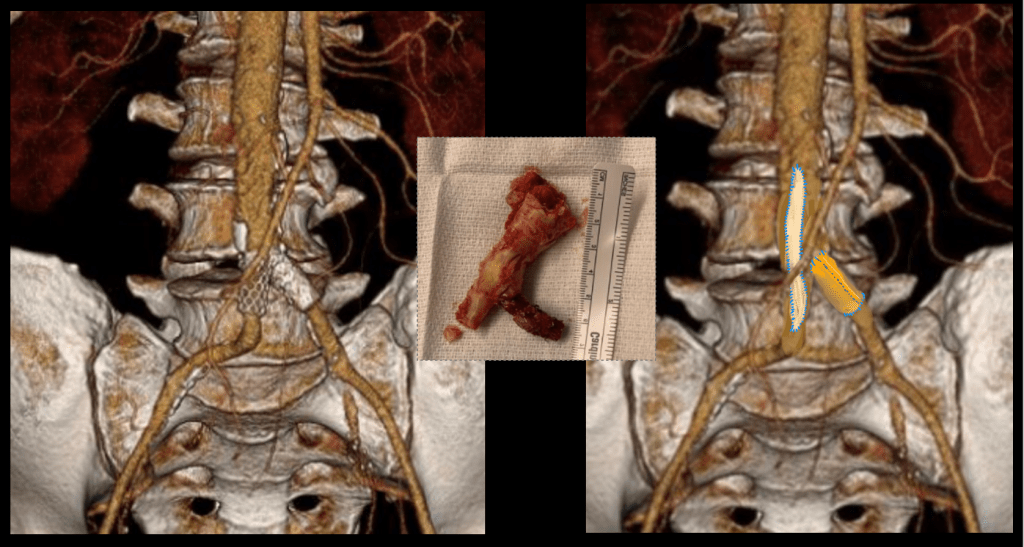

The image above shows a common femoral artery aneurysm presenting as a pulsatile mass in the right groin. The first image on left is an arteriogram (a sketch of one) that I would get prior to surgery. The patient is also suffering from pain in the right leg due to a lack of blood flow because his superficial femoral artery (SFA) is occluded and his profunda femoral artery (PFA) is open but has a blockage at its origin where the aneurysm ends. I plan the surgery and execute it. During surgery, things may pop up -good things like finding an otherwise pristine SFA filled with plaque. Removing the plaque, it becomes a great conduit for replacing the aneurysm and avoids using an expensive graft which can become infected -your own tissues fight off infection better than graft.